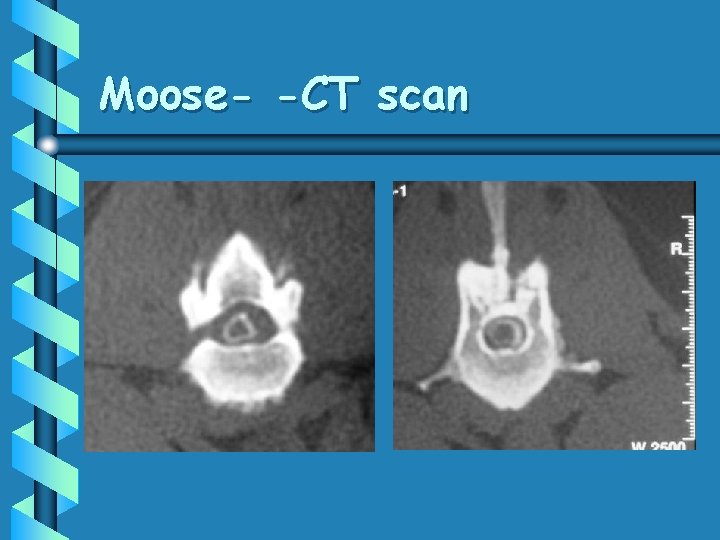

Moose • 9 year old M/C Labrador • HBC 4 months ago – Recovered • Chronic, progressive paresis over 2 weeks

Moose- -CT scan